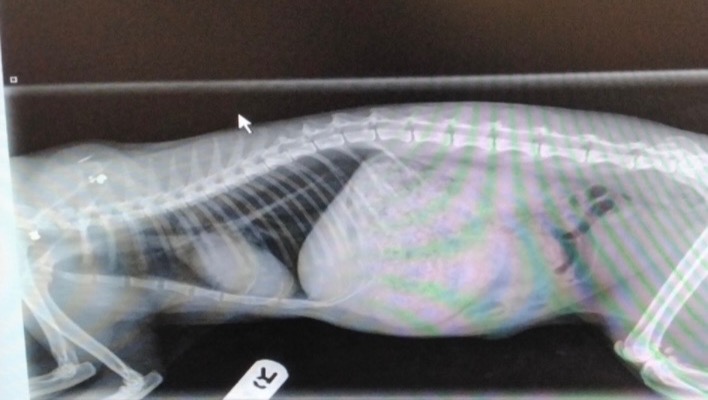

We took her straight to the vet who x-rayed her and confirmed that not only had Willow broken her left Tibia, but she also had two air rifle bullets lodged in her left shoulder.

Unfortunately, the pellets could not be removed as they are deeply imbedded.